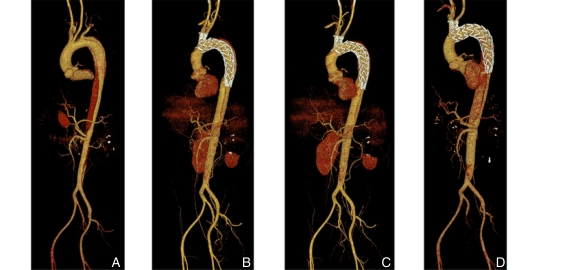

图1 典型患者CTA图像 A:术前;B:术后即刻;C:术后1个月;D:术后12个月Fig.1 Representative CTA images of a typical patient A: Preoperative image; B: Immediate postoperative image; C: One-month postoperative follow-up; D: Twelve-month postoperative follow-up